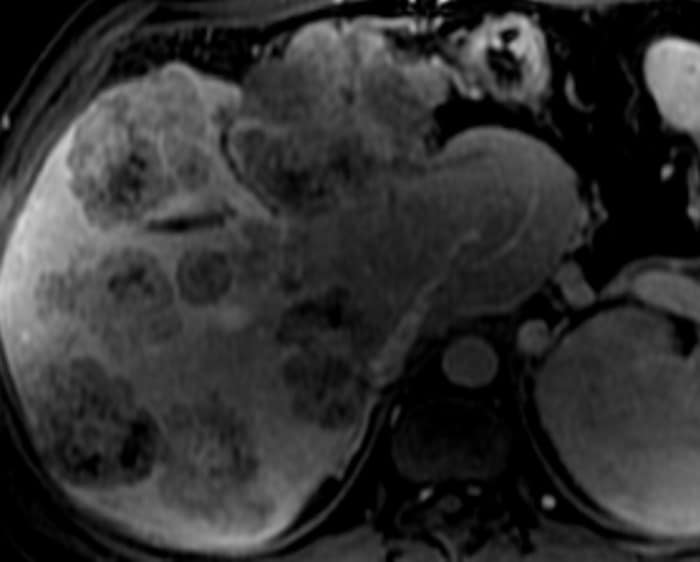

Di căn gan

» Thông tin: Nam giới – 37 tuổi.

» Lâm sàng: Tiền sử K đại tràng.